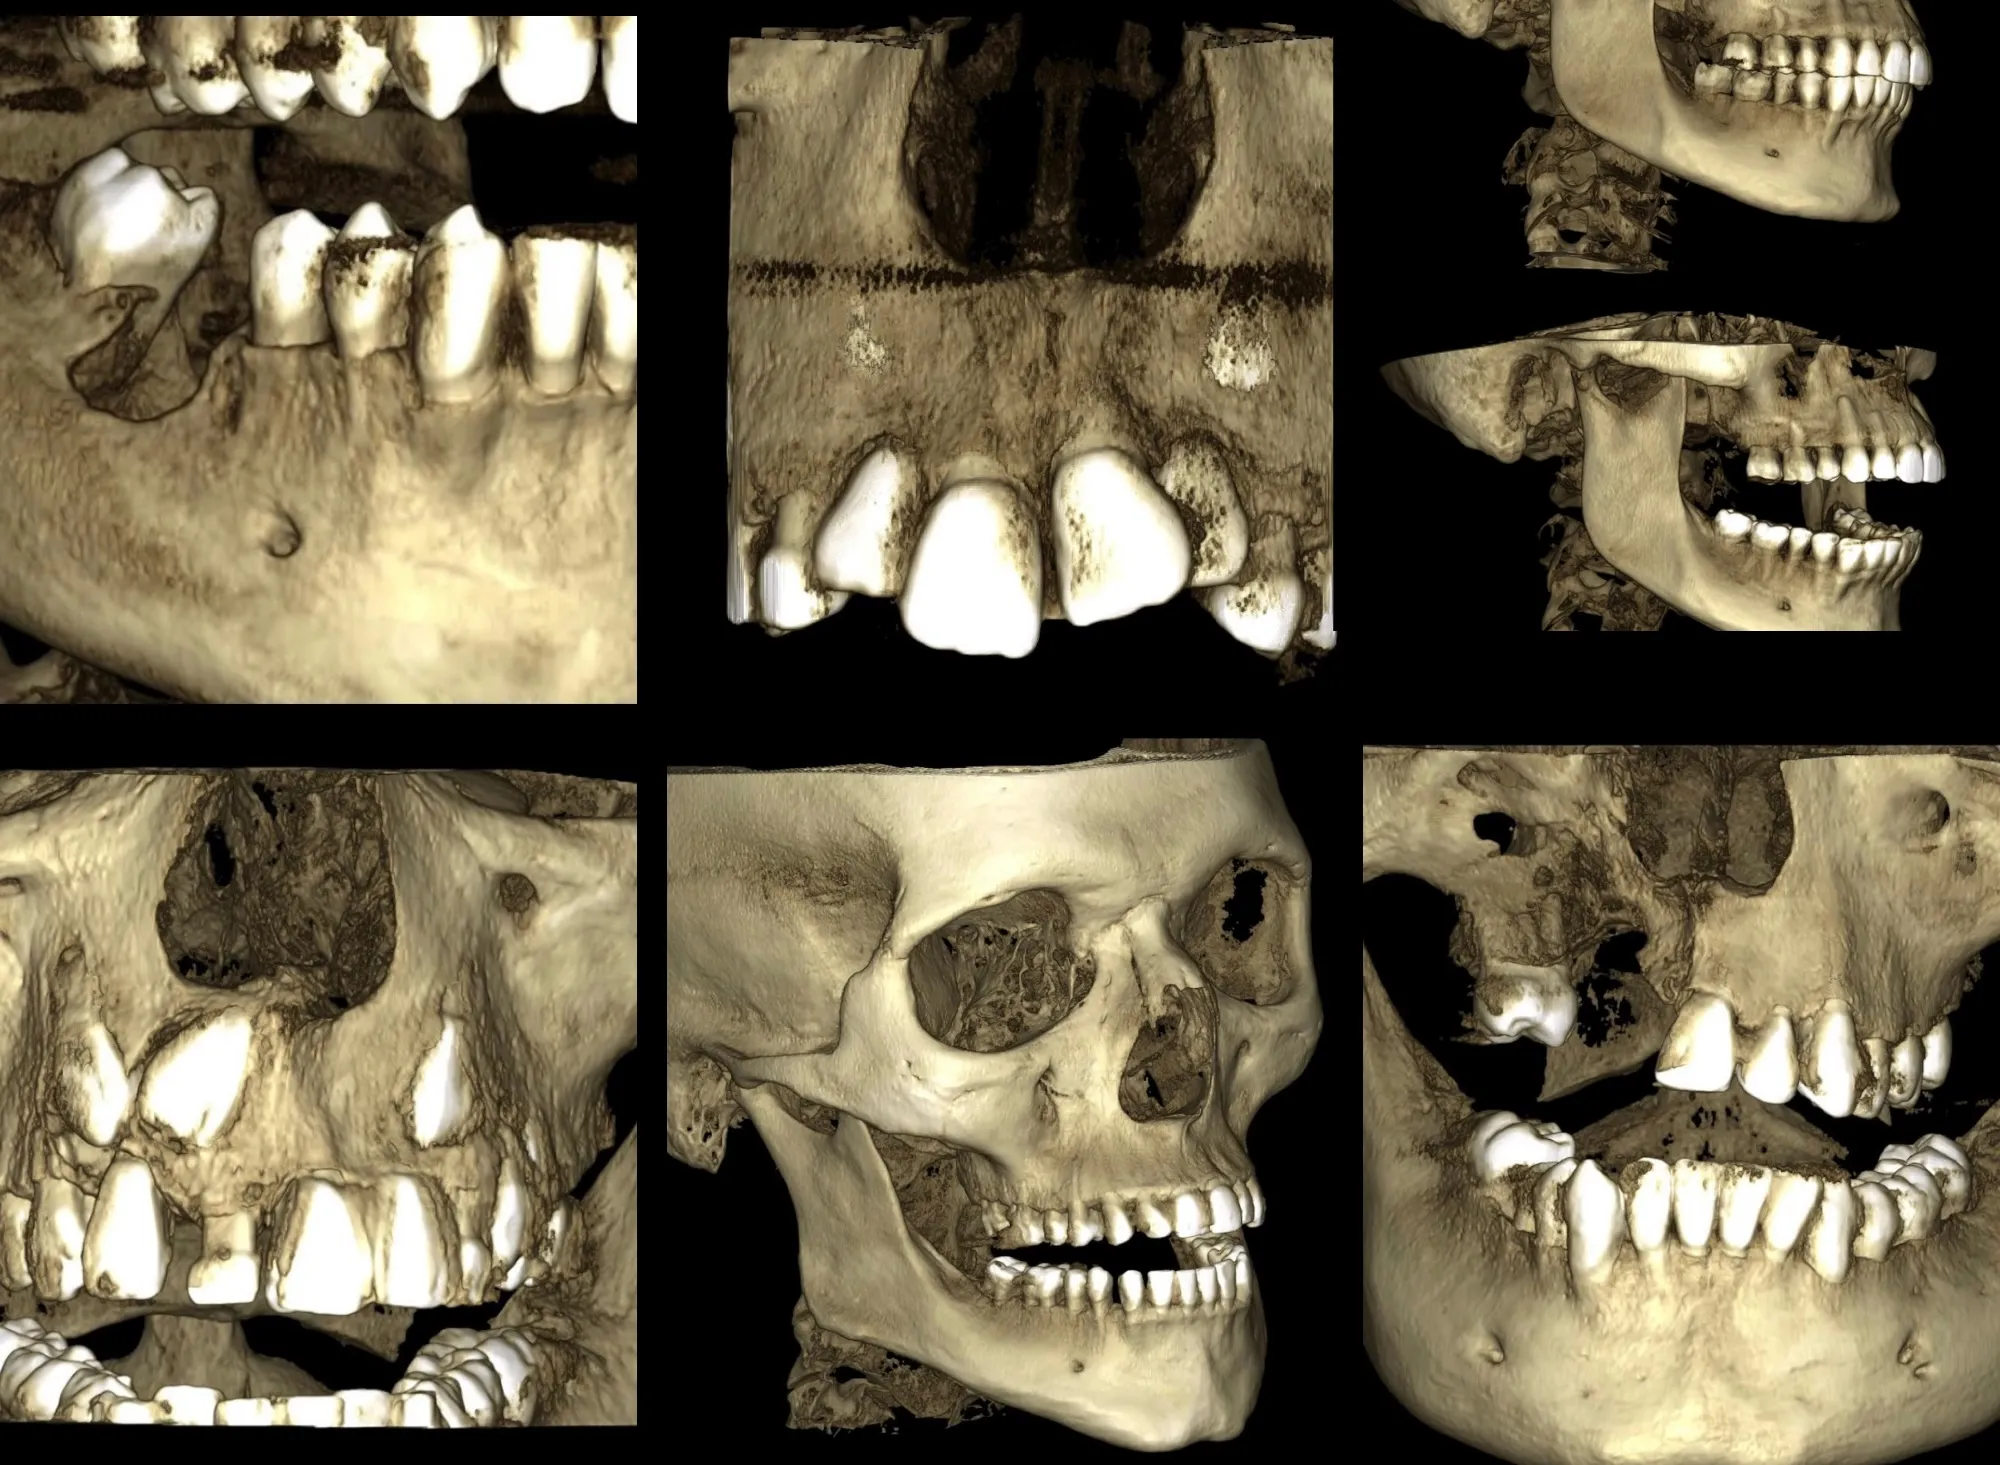

Radiopacas intraósea

Presencia de 3 imágenes radiopacas intraósea de densidad dentaria compatible con odontomas compuestos proyectados.

• 2 en zona de pieza 11

• 1 en zona de pieza 43

Odontoma Compuesto

Imagen hiperdensa localizada en el maxilar superior izquierdo, ocasionando el desplazamiento de la tabla ósea bucal y desplazamiento palatino de la pieza 2.4.